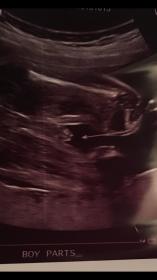

I just want to get other people's opinions. I have been told boy by the techs but people keep bothering me saying my baby doesn't look like a boy. Attachment 33349Attachment 33350Attachment 33349Attachment 33350

What do people think that is then? That is very BOY.

Looks very boyish to me, scrotal sac and a penis! Congrats x

All boy

Looks very boyish to me. Congrats